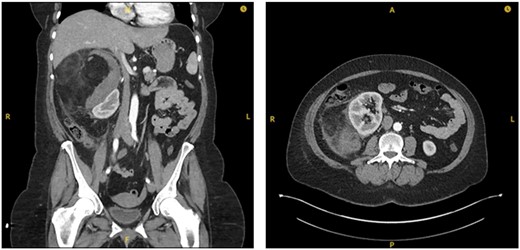

The patient was subsequently transferred over to the local specialty Urology Centre. Here the patient became tachycardic and required supplemental oxygen. A suspicion of increasing blood loss or a pulmonary embolism (PE) was raised. A repeat CTAP in arterial and venous phases along with a CT pulmonary angiography (CTPA) was conducted. The CTAP again showed a large right-sided retroperitoneal mass, now described as mixed fat and soft tissue densities characteristic of AML. The surrounding retroperitoneal bleeding was thought to have increased in size, indicating likely active haemorrhage (Fig. 2). CTPA showed no PE.

Sequential transverse sections of CTAP in arterial phase showing extent of lesion down to level of right Ilium bone.